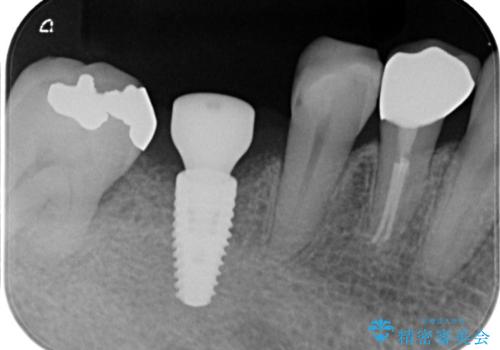

- 定期的に本院に通院されている患者様で、前歯の揺れがあると相談されました。下の奥歯が左右合わせて3本喪失されており、噛み合わせの負担が前歯にも集中していることを説明しました。右下6番の歯に関しては、事前の診査で十分な骨量がありましたのでインプラントを1本埋入しました。左下5番・6番にも本来はインプラントを埋入したかったのですが、骨量が十分でなく、骨を増やす処置をすると神経が近くリスクがあることから、審美性に配慮した金属のばねが見えないノンクラスプデンチャーを製作しました。また、このとき入れ歯を支える左下7番に根尖病変がありましたので、根管治療も行っております。(根管治療は当院院長で専門医を持つDr.林が担当しています。)治療終了後、約1年が経過しましたが、問題なく経過しており患者様も喜ばれていました。